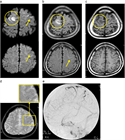

1. 脳静脈血栓症はCTやMRIにて診断を行う。特に、MRIのT2*強調画像Susceptibility-Weighted ImageSWIとMRV(magnetic resonance venography)、あるいはCTV(CT venography)でまず診断を行い、必要に応じて脳血管造影を行うことが推奨される(推奨度1)